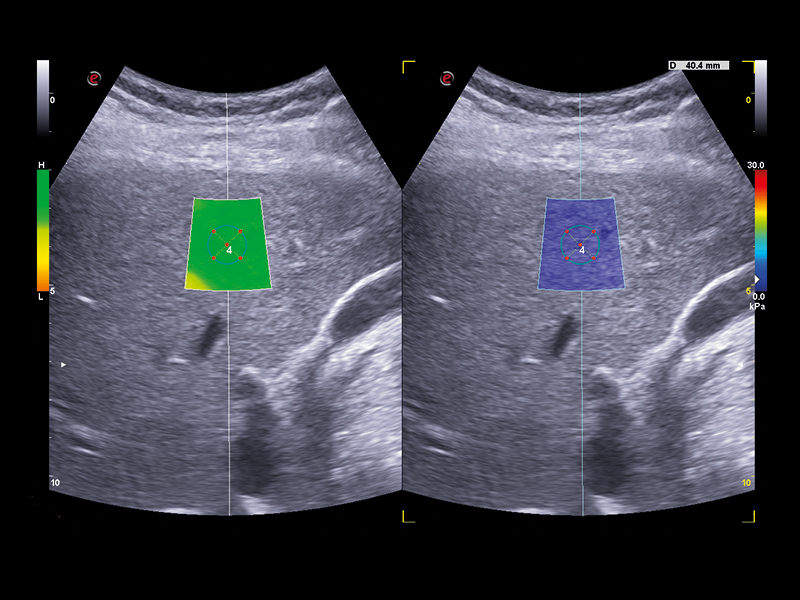

Esaote offers a comprehensive real-time multiparametric package to assess the liver tissue in a non-invasive way. QElaXto 2D, Esaote’s Shear Wave Elastosonography (SWE) technique enables stiffness mapping and provides a quantitative assessment of liver fibrosis.

A strong rejection algorithm associated with a dispersion map increases the quality and reliability of the measurements. QAI (Q Attenuation Imaging) is an ultrasound technique for the visualization and quantification of the attenuation along the liver depth provided by Esaote, to support the evaluation of fatty liver tissue and help in the steatosis assessment. The data are computed in a clear multiparametric report with a spider or bar-graph representation to obtain an overview of the liver condition at a glance.